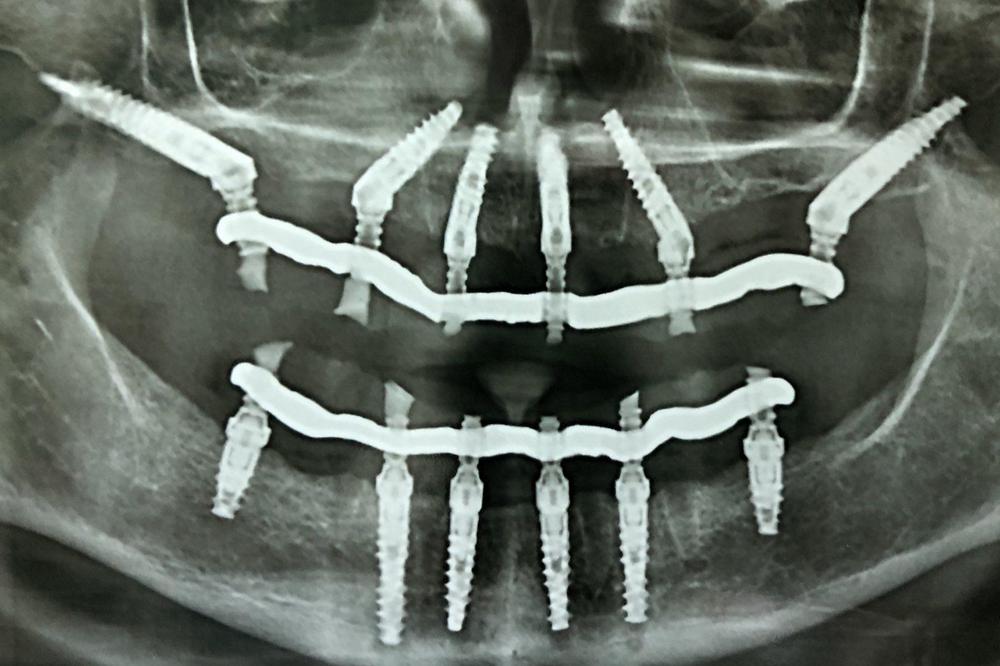

При изучении данных 3D-исследования, был выявлен недостаток высоты и толщины костной ткани на обеих челюстях. В связи с этим пациентке был предложен вариант быстрого и эффективного восстановления зубов на верхней и на нижней челюстях с использованием методики All-on-6 (все на 6-ти): были удалены оставшиеся зубы, установлены 6 имплантатов на верхней и 6 имплантатов на нижней челюстях, в течение 5 дней изготовлены и зафиксированы в полости рта несъемные эстетичные и функциональные протезы на обе челюсти. Таким образом, пациентка обзавелась красивой улыбкой за 5 дней.